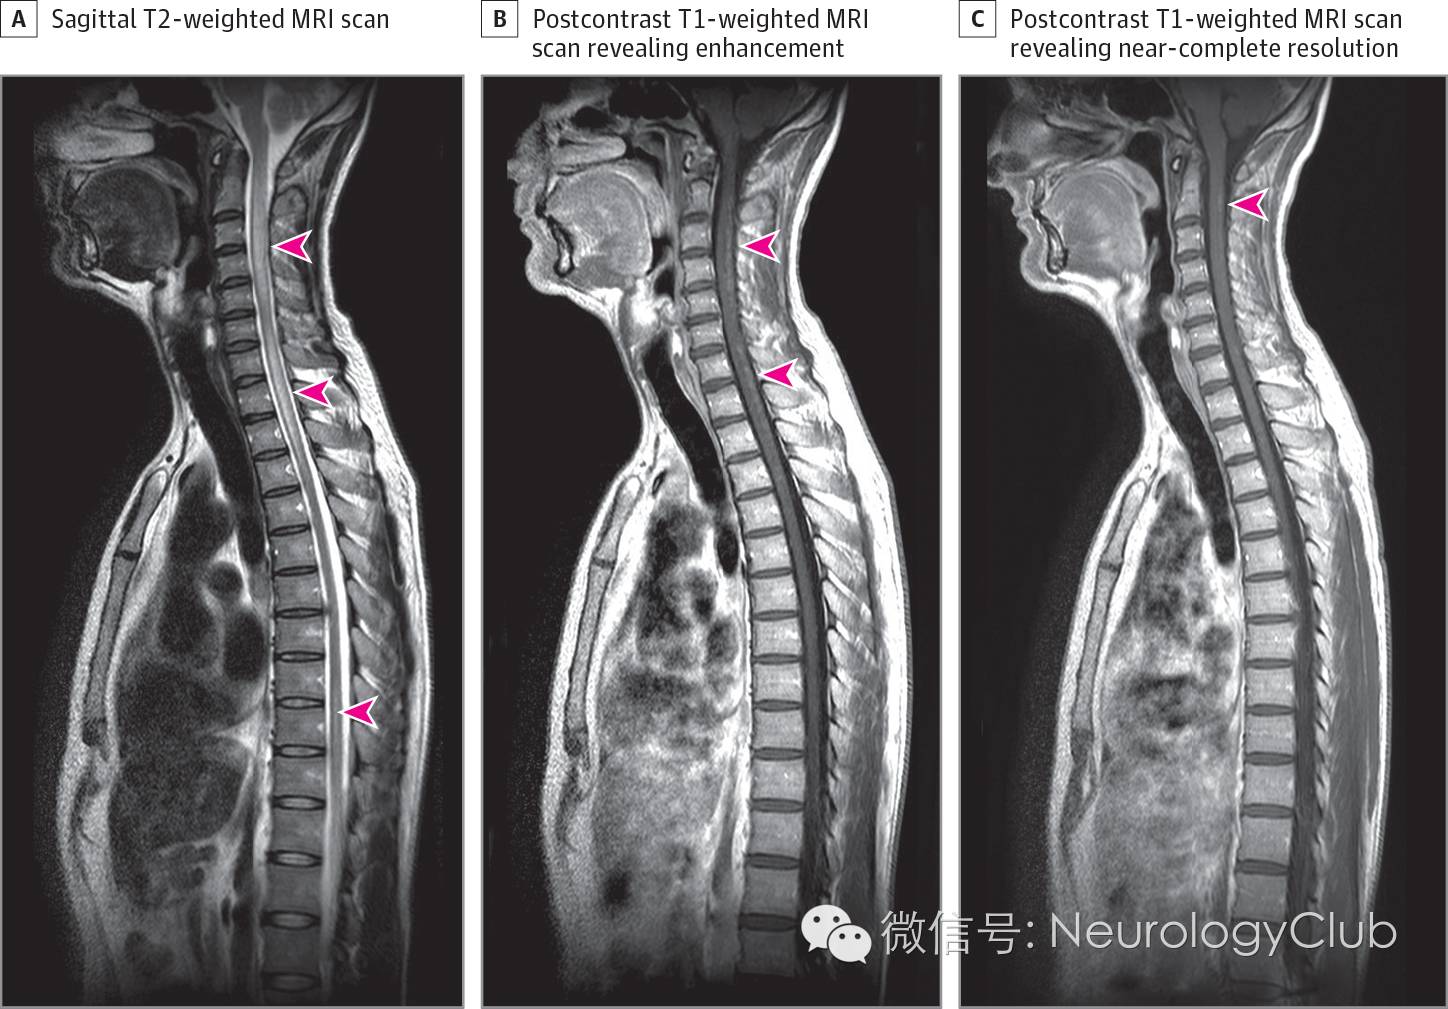

40余岁男性患者,因进行性腿部感觉异常伴主观性腿部无力4月入院。神经系统查体无殊。头颅MRI和实验室检查(包括水通道蛋白4抗体)正常。脑脊液检查提示轻度蛋白升高(0.7g/L),细胞数增多(白细胞48/mm3,95%为中性粒细胞)以及3条寡克隆带(镜像分布)。脊髓磁共振提示长节段脊髓病变伴C2-C5和C7-T3水平水肿以及脊髓背柱非连续性片状强化(图1)。胸部X片和血清血管紧张素转化酶正常。胸部CT提示肺门淋巴结肿大,且在氟脱氧葡萄糖PET上可见摄取增加。

(图1:A:矢状位T2WI可见长节段脊髓高信号病变累及数个椎体节段[箭头],伴C2-C5和C7-T3水平水肿;B:T1增强可见脊髓背柱不规则片状强化[箭头];C:类固醇激素治疗12天T1增强上病灶几乎完全消失[箭头])

经支气管淋巴结活检证实为非干酪样肉芽肿,符合结节病(图2)。静脉给予甲强龙(1g/d,连用5d),症状好转,复查MRI病灶近乎完全消失。随后患者接受硫唑嘌呤和强的松治疗。随访2年,患者病情平稳,未再复发。

本例患者中,起病时一些典型的磁共振表现,例如脊髓梭形增粗和脊髓背柱不同程度的结节状强化(提示病变来源于软脑膜),可高度符合神经结节病。提高对脊髓结节病的认识,并给予恰当的类固醇激素和免疫抑制治疗,对预防脊髓萎缩和改善预后而言非常重要。